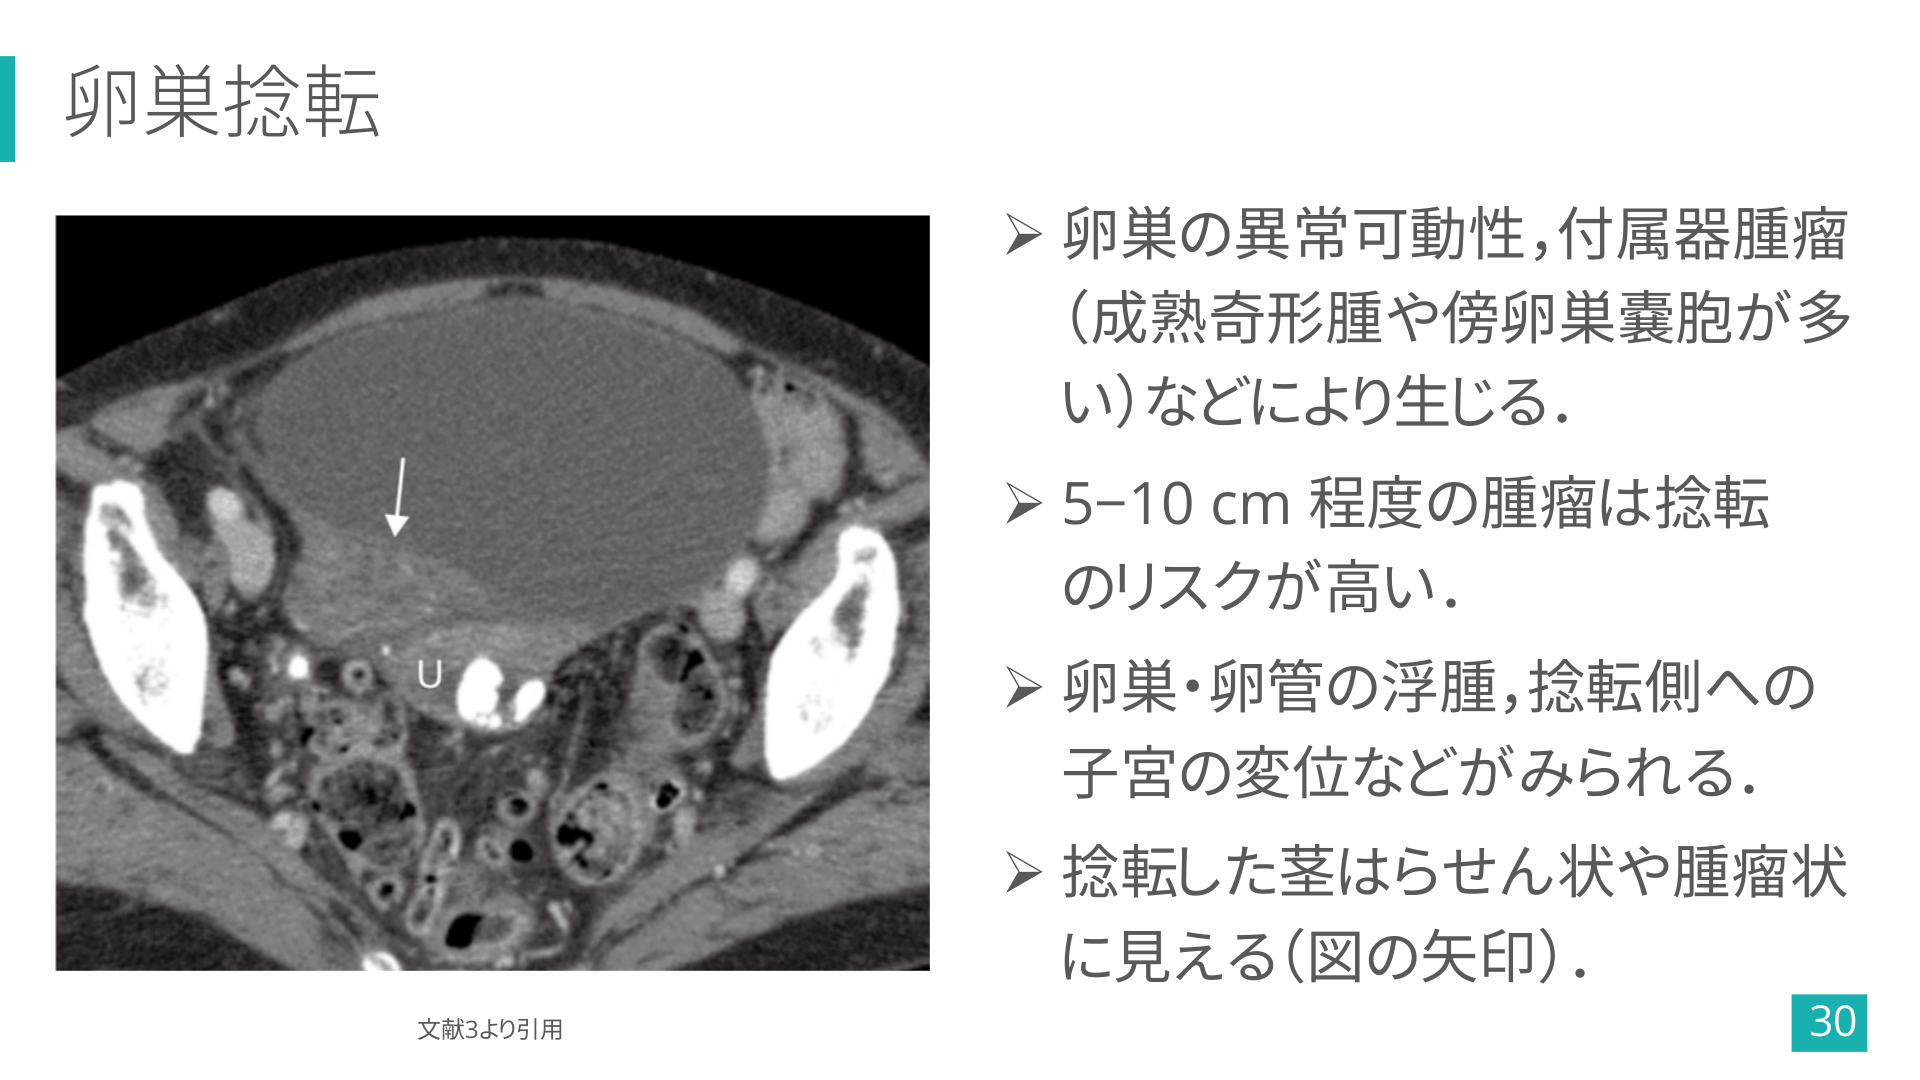

卵巣捻転 Ø 卵巣の異常可動性,付属器腫瘤 (成熟奇形腫や傍卵巣嚢胞が多 い)などにより生じる. Ø 5−10 cm 程度の腫瘤は捻転 のリスクが高い. Ø 卵巣・卵管の浮腫,捻転側への 子宮の変位などがみられる. Ø 捻転した茎はらせん状や腫瘤状 に見える(図の矢印). 文献3より引用 30